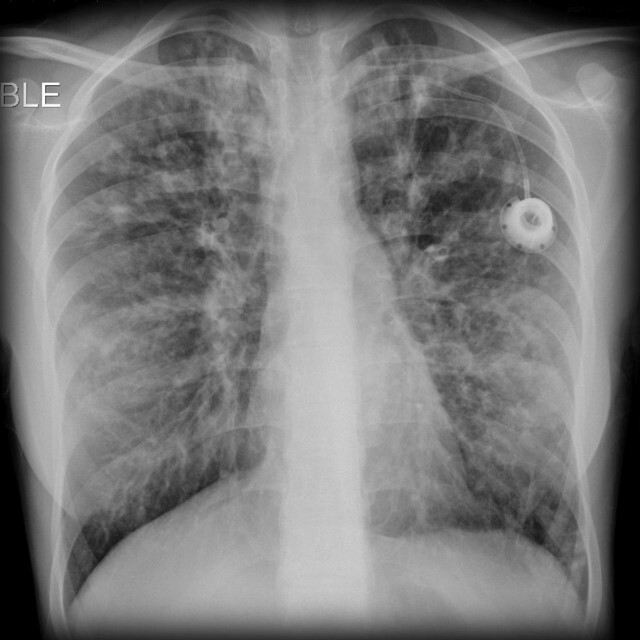

What pathology is seen here?

Interstitial Pneumonia